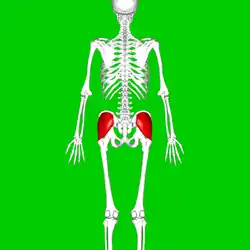

Les nerfs su membre inférieur. Vue postérieure Posterior view. Vue anatomique du dos.

Vue anatomique du dos.